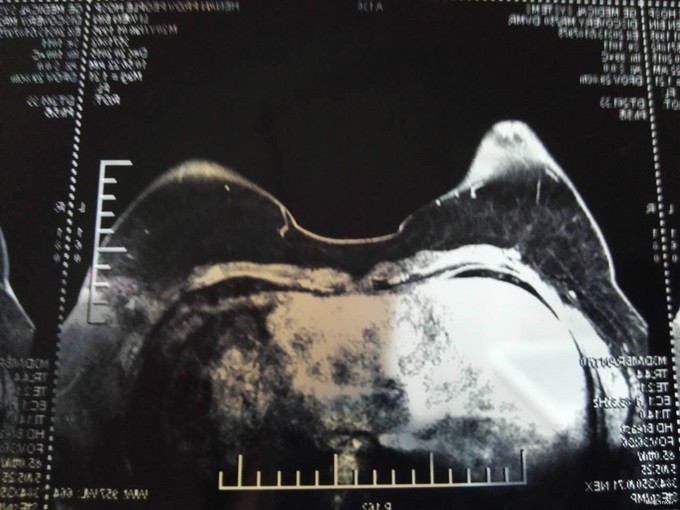

双乳基本对称,乳房呈“女性化”发育,乳头在同一水平线上。阴茎短小,未发育,无体毛。行MRI示:双乳腺体异常发育。性激素提示:睾酮 0.19ng/ml(正常成年男性 1.75-7.81ng/ml)。

入院后完善术前相关检查,无明显手术禁忌症,全麻下行“双乳腺体大部分切除术”,术后病理:双乳符合男性乳腺发育。